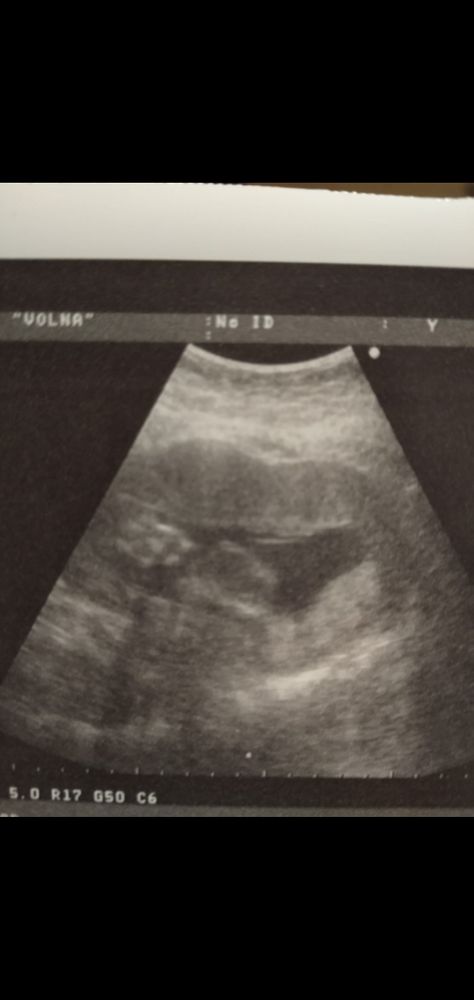

Девочки посмотрите кто у нас?Ну уж очень интересно) Половой бугорок

Ксения Тамаревская, хи, фига, а мне по последнему УЗИ в среду кажется что голова там, у гинеколога правда не очень аппарат, так типа одним глазком посмотреть Изображение